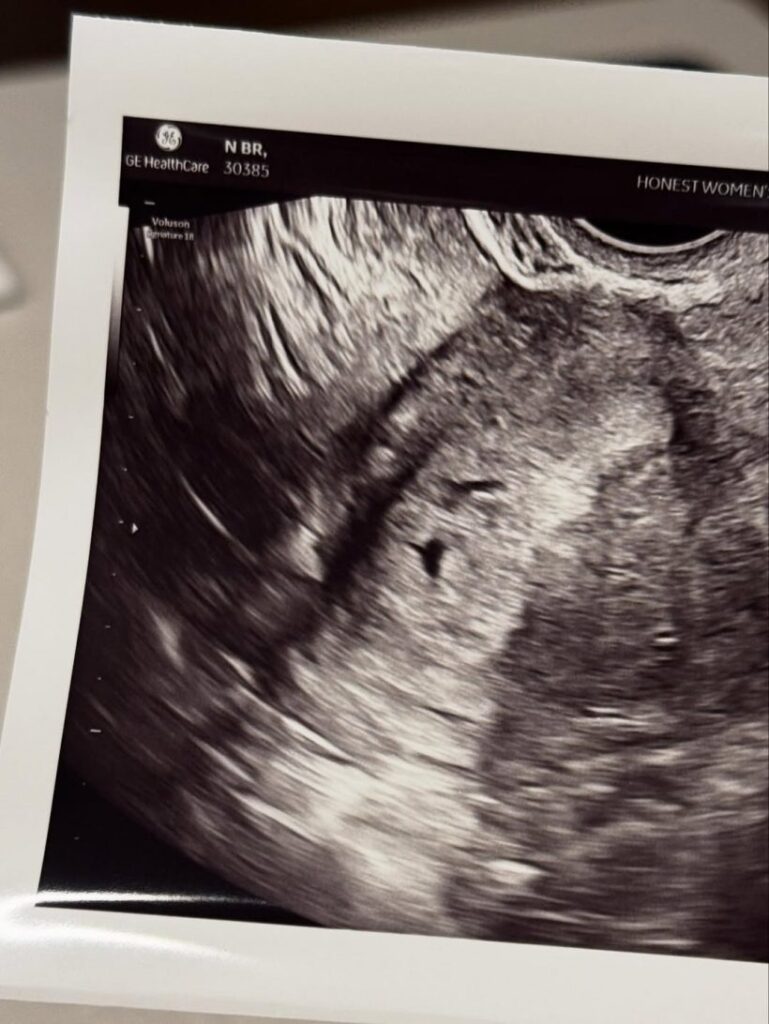

เธอได้โพสต์ภาพปาร์ตี้ประกาศข่าวท้อง และภาพอัลตราซาวนด์ให้แฟน ๆ ได้ร่วมยินดี ซึ่งก็ได้รับคอมเมนต์อวยพรล้นหลาม